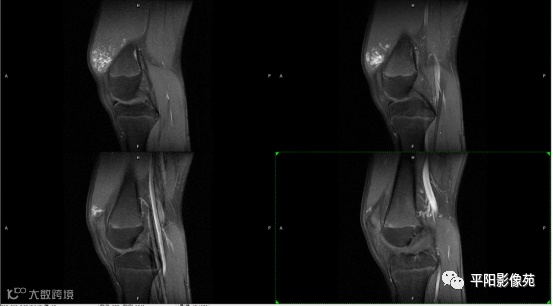

影像表现:

左膝关节股内侧肌内见多房样短T1长T2信号,内可见分隔,增强扫描明显强化,分隔未见明显强化,病灶局部与股骨远端分界不清。

MRI表现:好发于下肢, 较大病灶多为与肢体长轴一致的梭形, 边缘不清, 较小病灶呈类圆形, 边缘较清;②T1WI呈等或稍高信号, 病灶内部或边缘可见线条状或花边状高信号灶, 类似于皮下脂肪信号, T2WI上为明显高信号, 为本病特征性MRI表现;③病灶内静脉石及血管流空影为又一特征MRI表现;④GD-DTPA增强, 病灶明显强化, 其内低信号间隔无强化;⑤可见骨外形改变, 骨质增生及骨质吸收等表现。